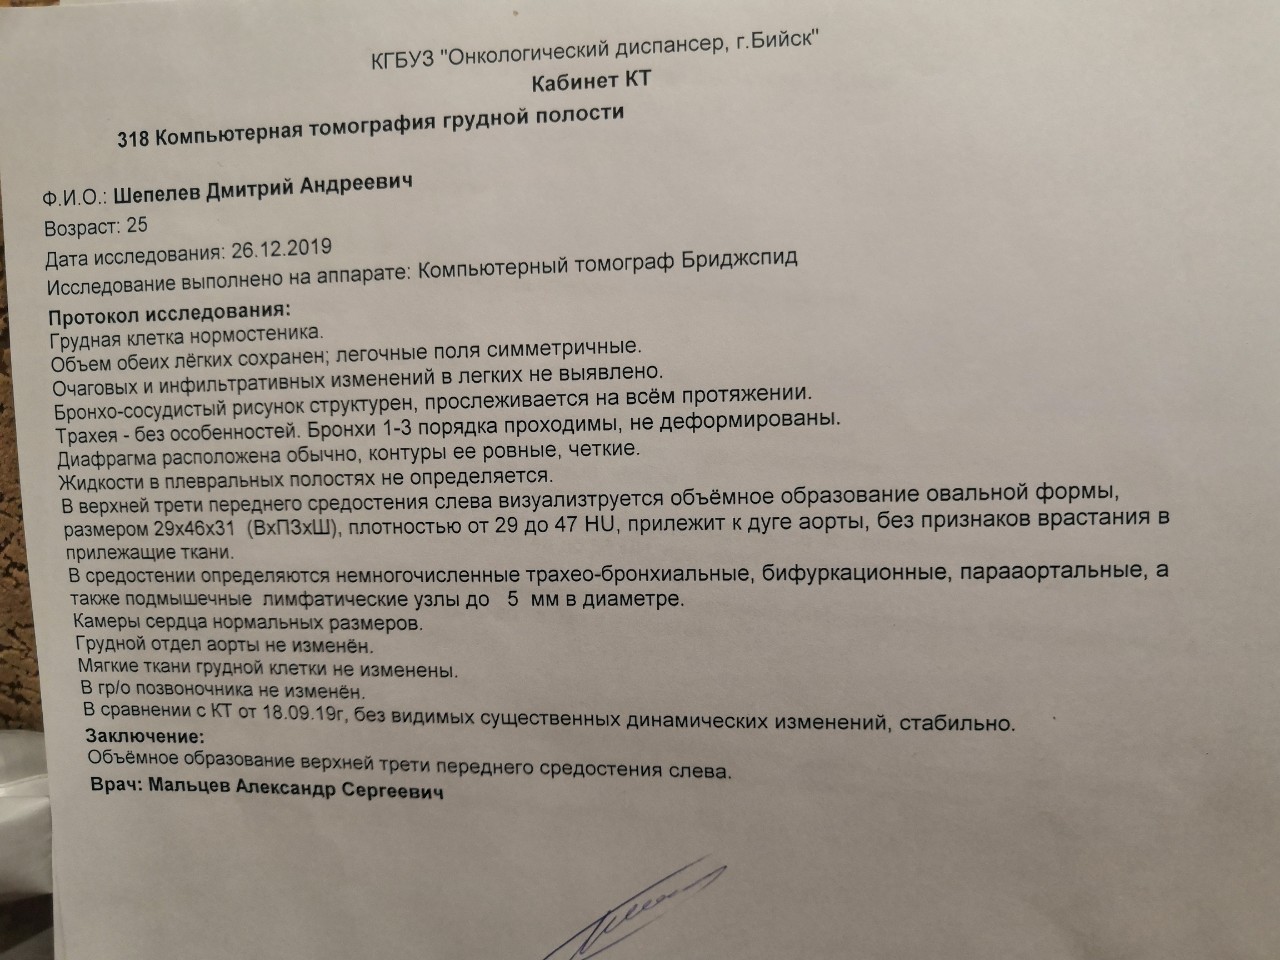

Раздел: Образы вокруг